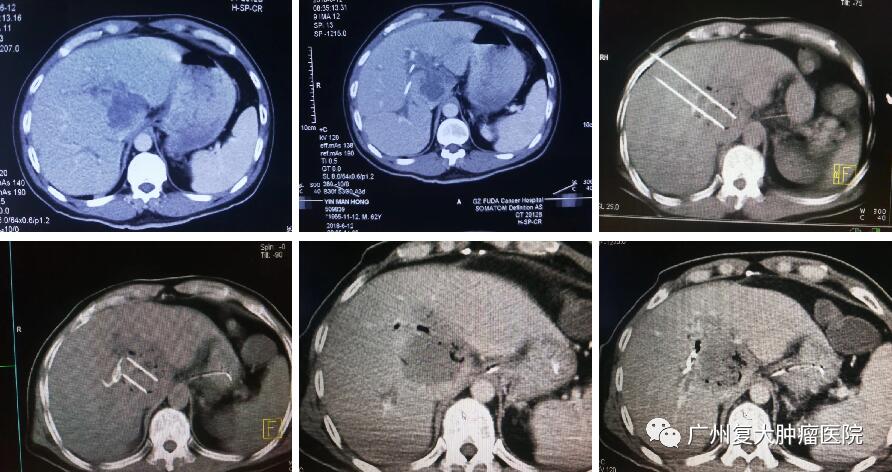

纳米刀已被美国、欧盟等国家和地区批准进入临床应用。2015年,广州复大肿瘤医院率先引进纳米刀技术,并应用于胰腺癌、肾癌、肺癌及肝癌的治疗,其中完成治疗近千例,肝癌治疗380例。而随着纳米刀治疗肝癌案例的增加,国内外领域专家对于邻近肝门部、血管及胆管旁癌灶消融的有效性和安全性一直在持续观察、评估及讨论。

当然,纳米刀相关机制、理论、最佳的参数以及其治疗的安全性和疗效还需要进一步研究及更多的循证医学证据。纳米刀治疗肝癌,因其无热吸除效应,可完全消融临近下腔静脉、大肝动脉或门静脉结构的肿瘤,且不损伤这些重要结构。对治疗靠近肝门区、血管、胆管等重要结构的肝肿瘤较传统的消融方法具有明显的优势。